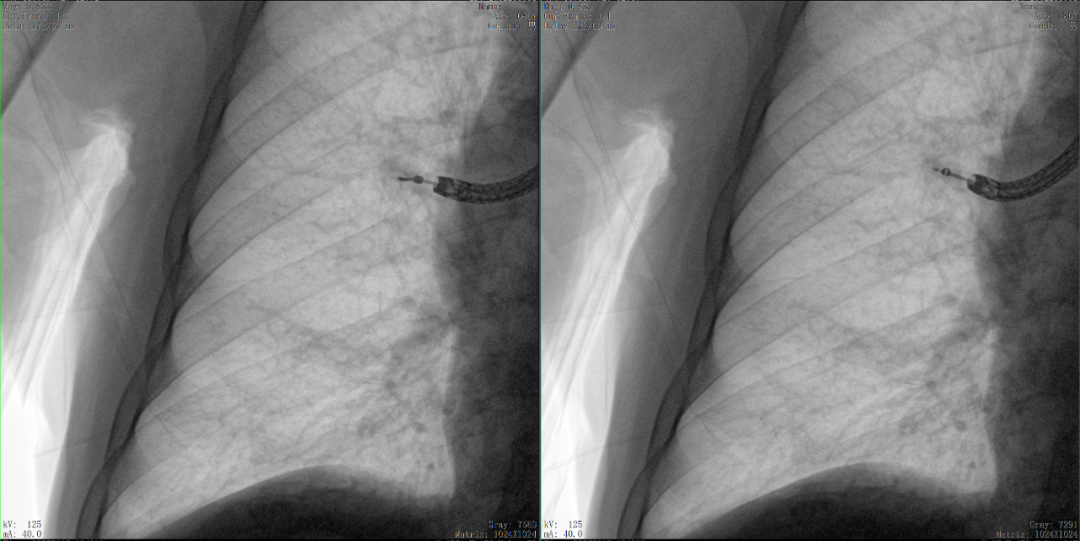

正侧位影像观察胫腓联合复位良好

从三维影像看,复位欠佳,贴合度不够

二维影像无法准确判断工具是否到达病灶